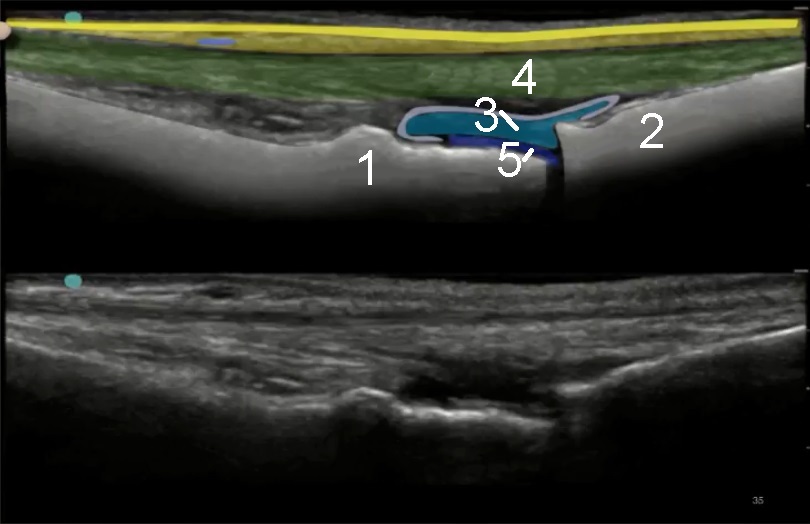

1. Distal Metatarsal Head

2. Proximal Phalanx

3. Joint Capsule

4. Extensor Tendon